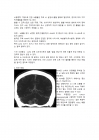

요약하면, AVM은 선천적 혈관 형성이상으로 인해 고속의 동맥혈이 모세혈관 없이 정맥으로 유입되는 병변이며, 뇌조직 허혈, 발작, 출혈성 뇌손상의 병태생리를 가지는 질환이다.

뇌동정맥기형으로 인한 뇌출혈은 주로 뇌실질 내 출혈 형태로 발생하며, 경우에 따라 지주막하출혈을 동반하기도 한다.

AVM은 CT에서 조영제를 투여할 경우 뇌실질 내에 복잡한 혈관 구조로 관찰된다.